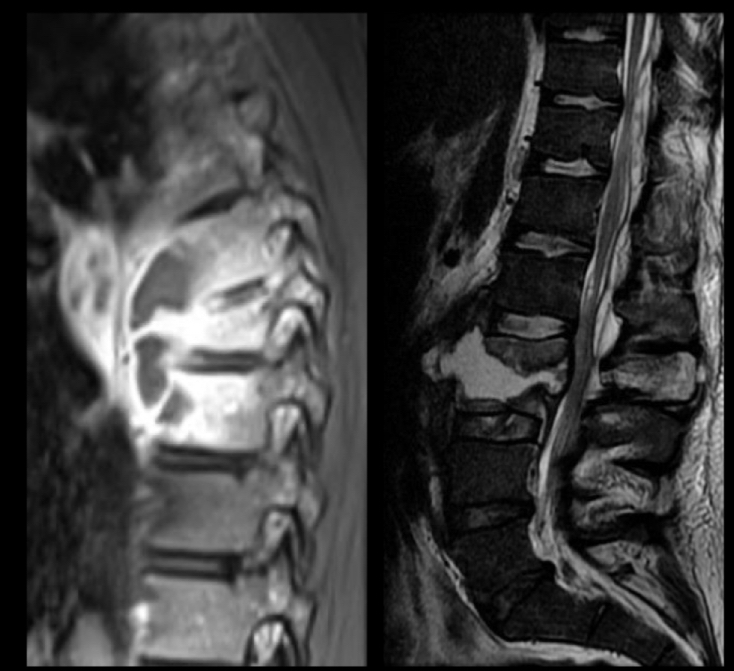

lo mejor de imagen para espondilodiscitis

A

RM con contraste

q se ve en RM de espondilodiscitis

• edema de medula

• Coleccion hipo en t1 e hiper en t2

• Permite distinguir de proceso degenerativo

• Permite valorar extension a estructuras adyacentes

• Capta contraste periferico

a q estructuras permite valorar la extension a estructuras perifericas la RM en una espondilodiscitis

psoas y medula

x q es mejor con contraste en una espondilodiscitis

xq forma absceso